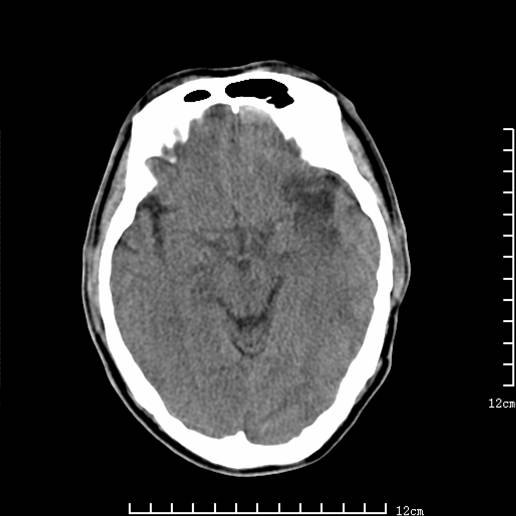

以下图像分别是3月25日凌晨及下午图像、3月27日、4月16日的ct图像。

3月27日